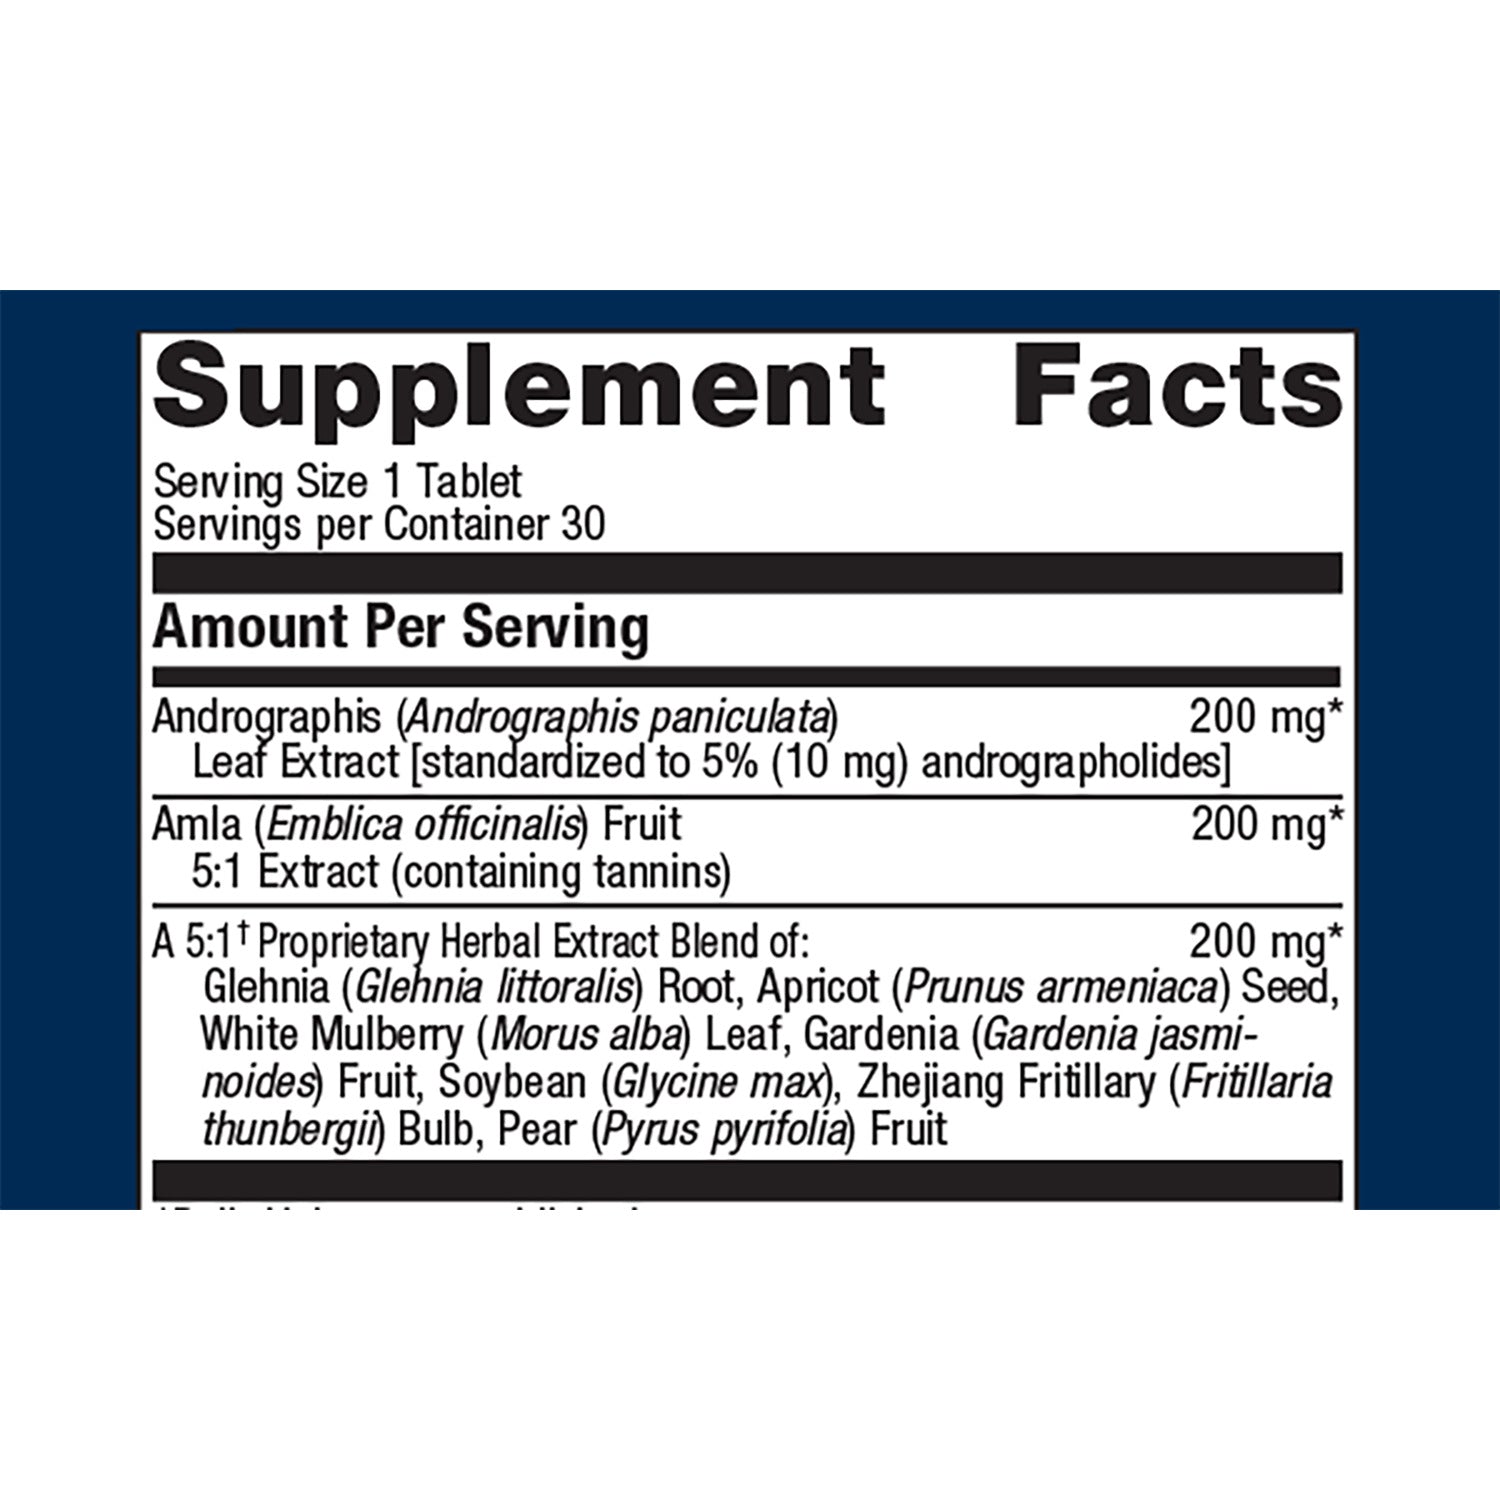

Andrographis Plus® delivers a proprietary blend of Ayurvedic and Asian herbs including concentrated andrographis extract and amla designed to support immune health. A proprietary herbal preparation traditionally used to support lung health rounds out this advanced immune support formula.

Ingredients: Microcrystalline cellulose, andrographis leaf extract, amla fruit extract, glehnia root extract, apricot seed extract, white mulberry leaf extract, gardenia fruit extract, soybean (soy), zhejiang fritillary bulb extract, pear fruit extract, cellulose, croscarmellose sodium, calcium silicate, stearic acid (vegetable), silica, magnesium stearate (vegetable), and coating (hypromellose, medium-chain triglycerides, and hydroxypropylcellulose). Contains: Soy.